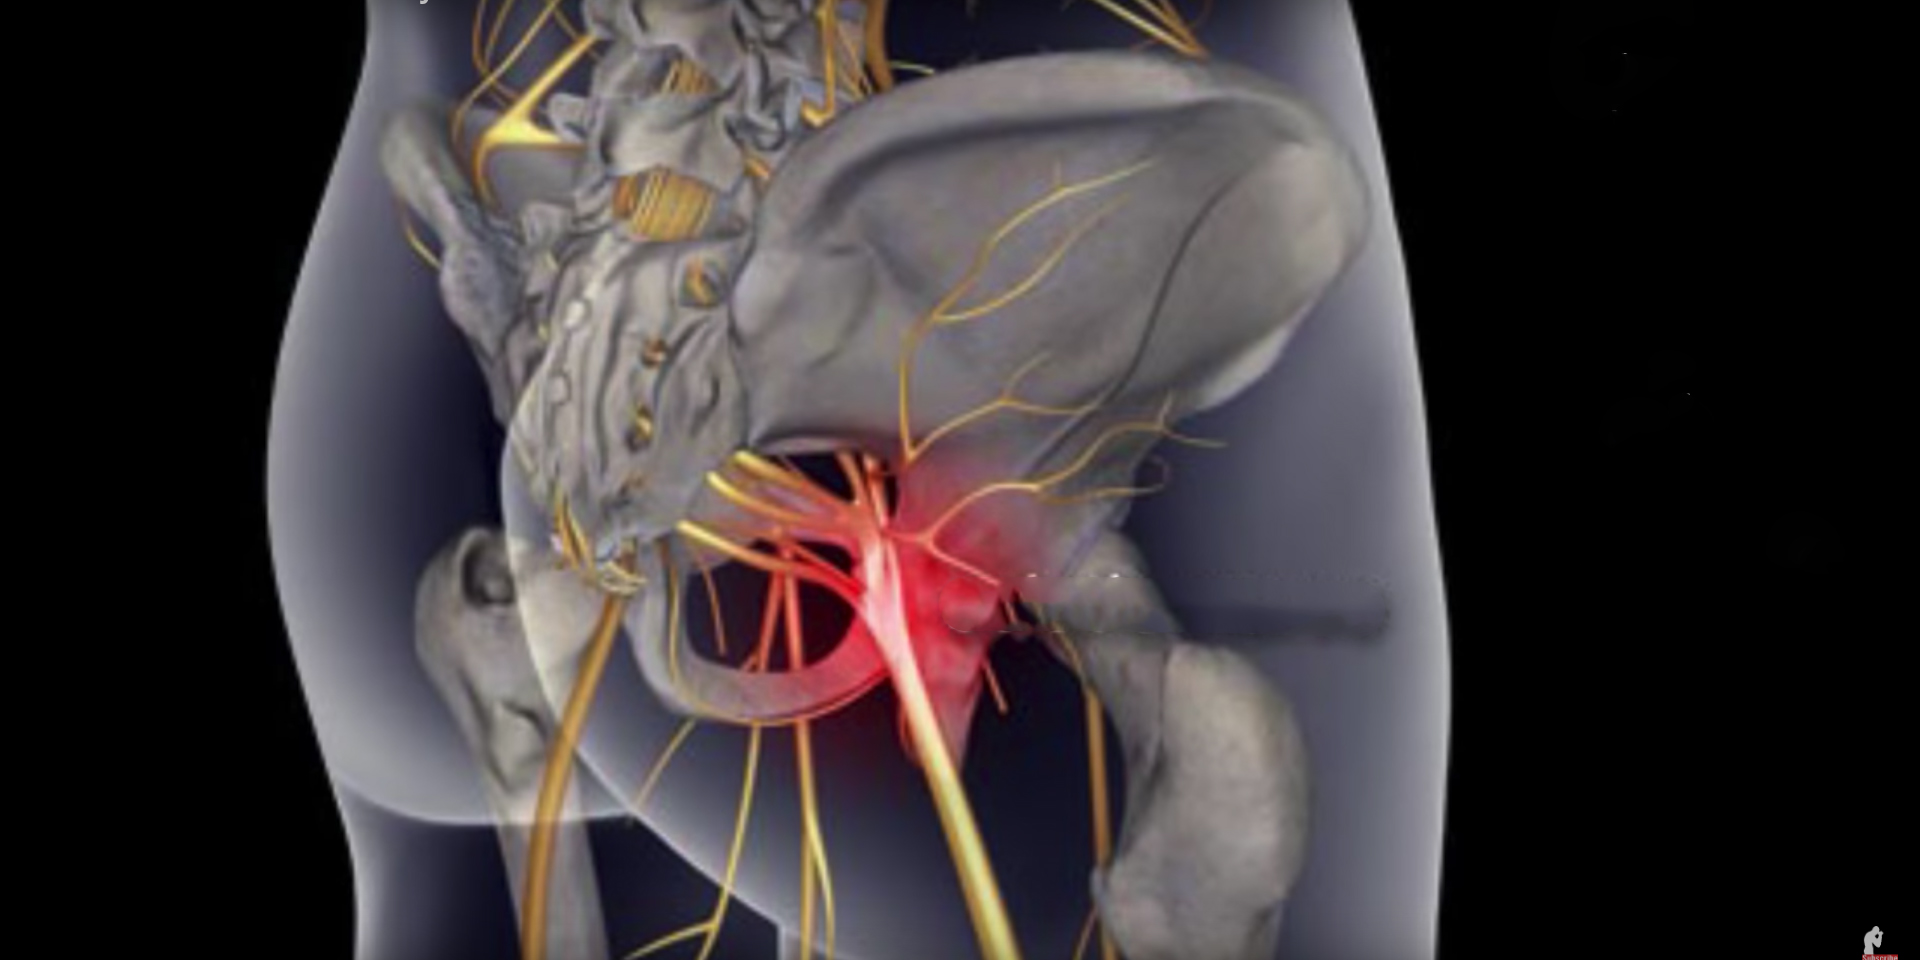

Боль в малом тазу у женщин: Причины и подходы к лечению